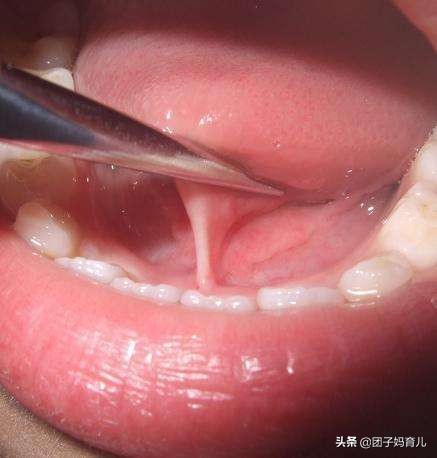

老人们口中说的“舌根”其实是——舌系带,也被称为舌筋。

孩子张口翘起舌头时在舌和口底之间的一薄条状组织,正常舌系带可以使舌头活动自如,舌尖能自然地伸出口外,或向上舔到上齿龈。